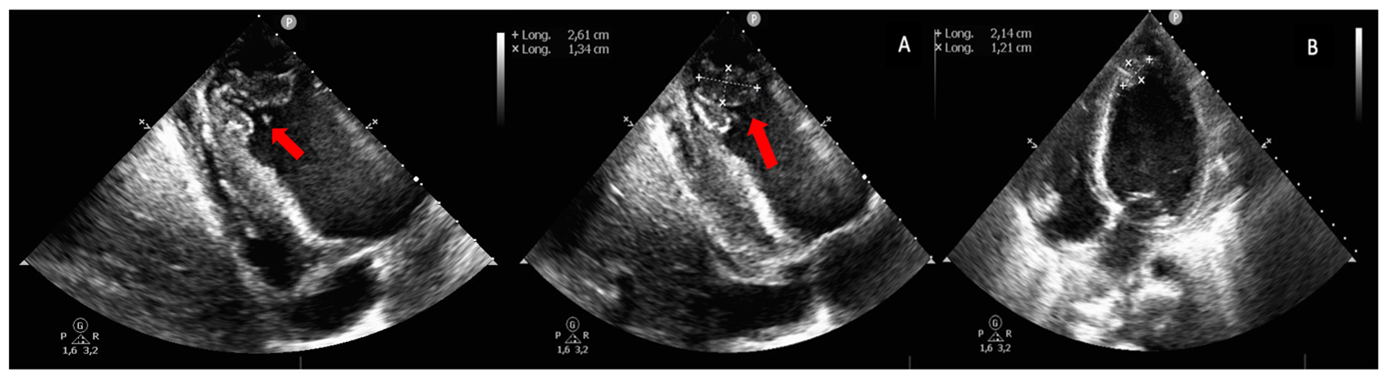

A cardiac ultrasound showed reduced contractility of the left ventricle, with left ventricular ejection fraction (LVEF) of 38% , global longitudinal strain (GLS) of -12% (Figure 2), along with significant spontaneous contrast and dilated left atrium. Additionally, two masses were identified at the apex of the left ventricle (LV) (Figure 3), and a third, larger mass was attached to the lateral wall of the right ventricle (RV) (Figure 4). The appearance of these masses was highly suggestive of thrombus, thus anticoagulation treatment was initiated.

Figure 3: TTE views showing two thrombi at the apex of the left ventricle (red arrow).